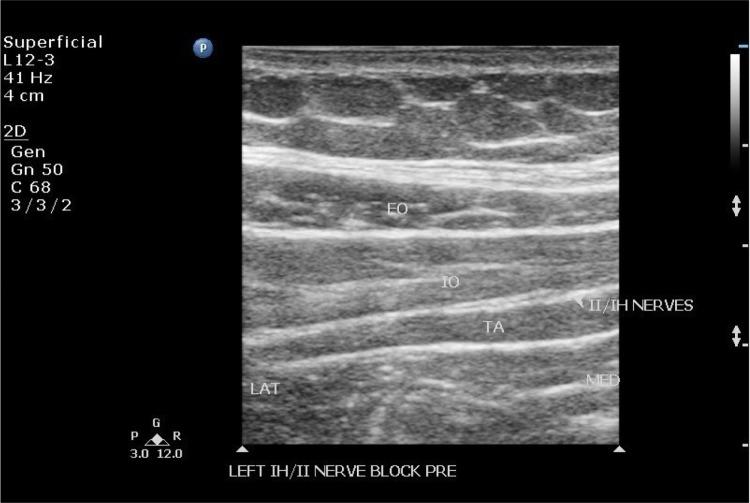

Landmark-based versus ultrasound-guided ilioinguinal/iliohypogastric nerve blocks in the treatment of chronic postherniorrhaphy groin pain: a retrospective study.

To compare the effectiveness of landmark-based and ultrasound-guided ilioinguinal/iliohypogastric nerve blocks in the treatment of CPGP.